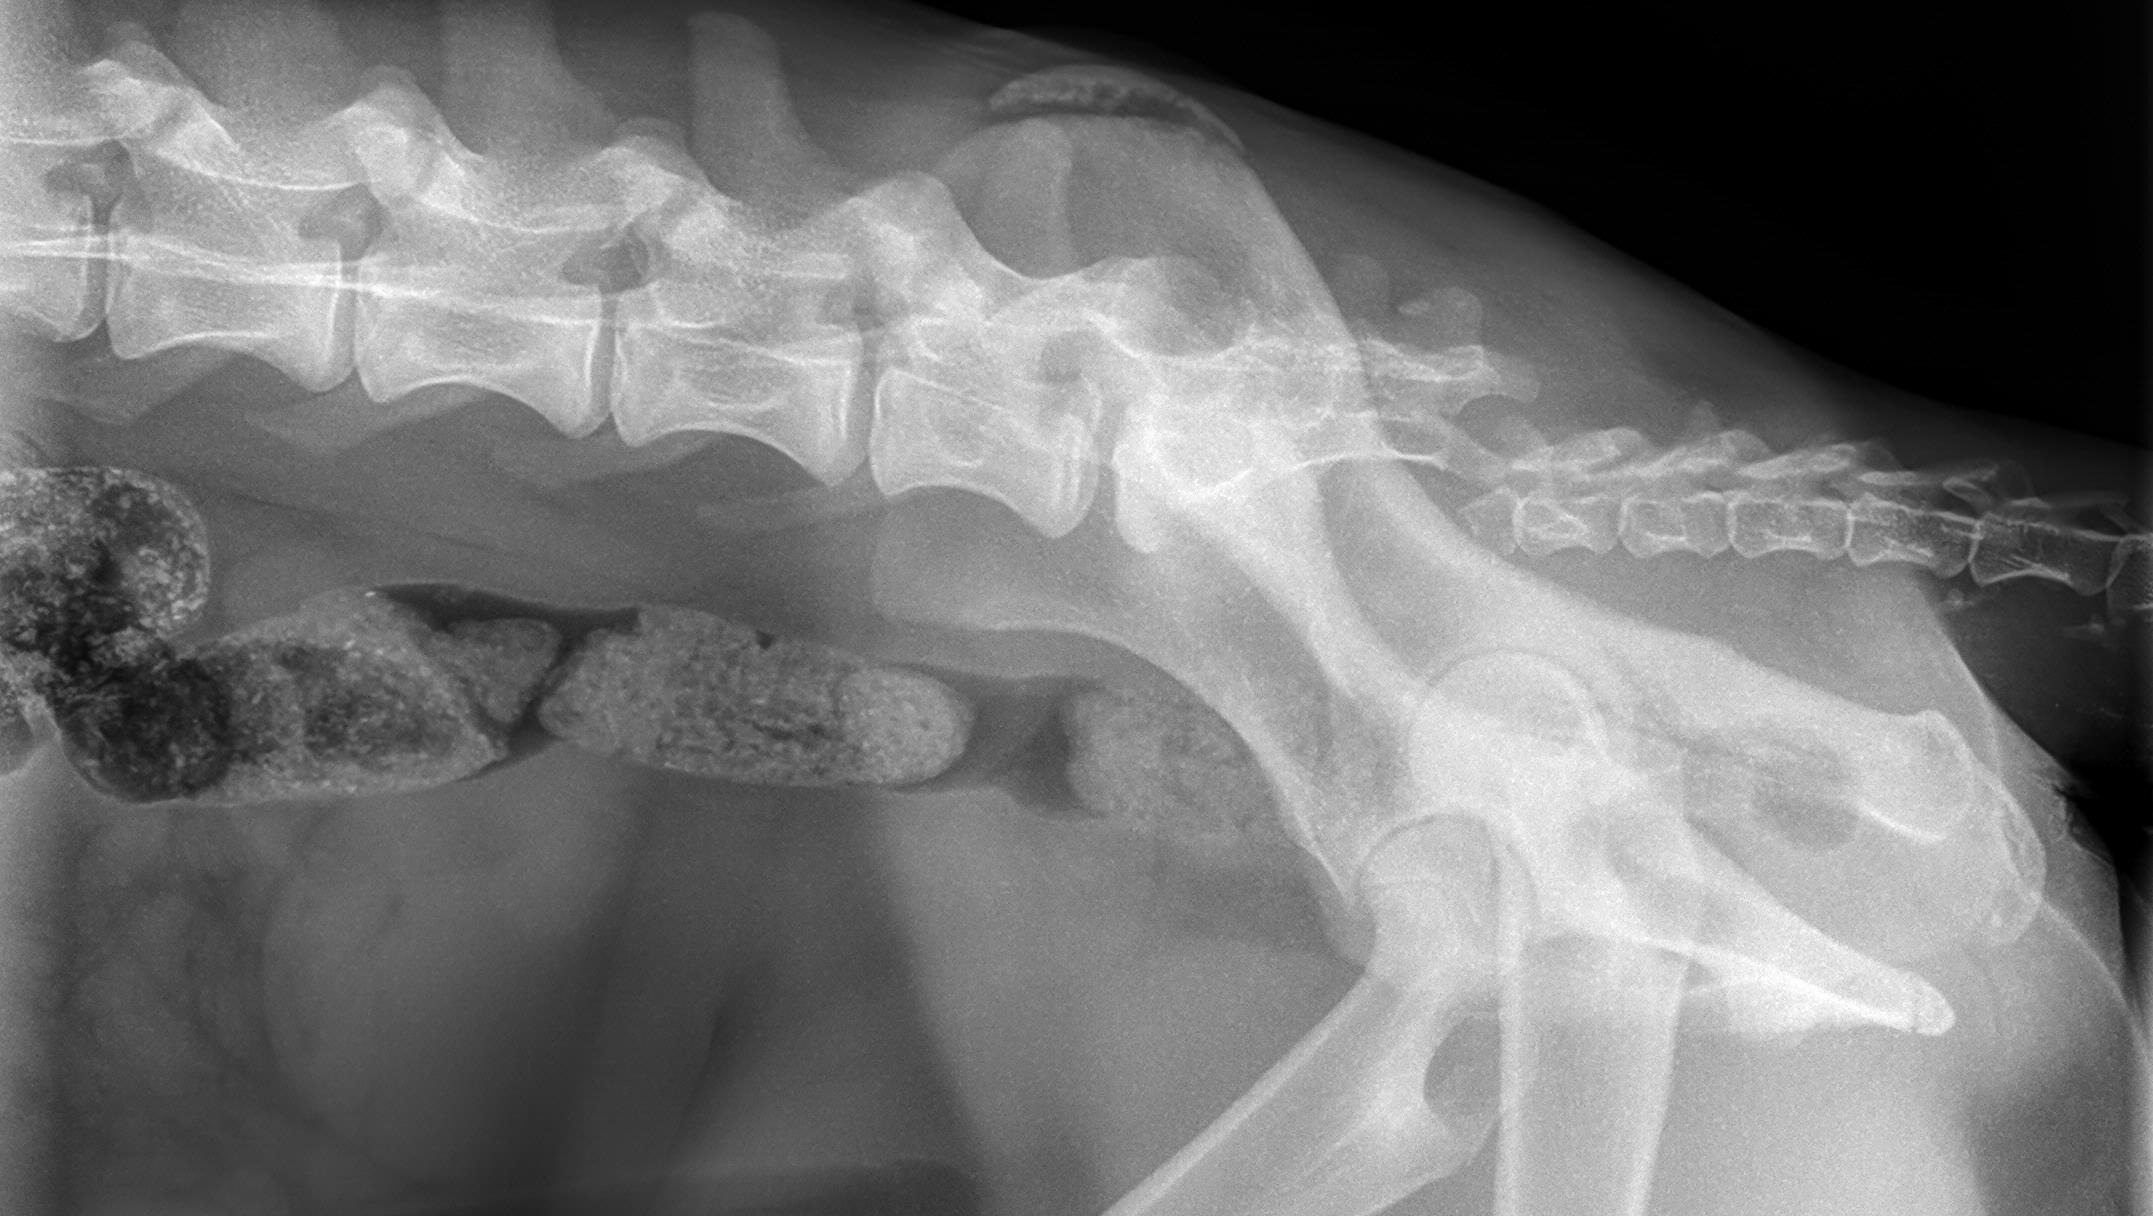

A few days ago, I found Honey on the side of the freeway after being hit by a car. She was beyond sweet and despite the pain, got up to greet me and snuggled between my legs. I immediately took her to the vet where they performed X-rays and determined she has a broken femur, a deep lesion on her tarsus, a dislocated tail, and paralysis of her hind end. This is all in addition to the malnutrition and dehydration she was suffering from due to being a stray for some time. She needs urgent orthopedic surgery to fix her femur, antibiotics for the lesion, and probable amputation of her tail. We've been reaching out to rescues to help, but she will likely be incontinent for the rest of her life so they're hesitant to help. She will need extensive care for the remainder of her life which we are more than happy to provide. She's already a member of the family. We really want to keep her, but she desperately needs these surgeries that we simply cannot afford right now! We're also worried that if we take her to a shelter they will put her down rather than fund these pricey surgeries. We've set a pretty high goal because the surgery is going to be expensive and she's going to require a lot of aftercare including a spay, licensing fees, medication, and measures for her incontinence.